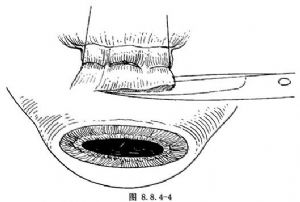

多采用角膜緣切口(圖8.8.4-1A、B),也可距角膜緣4~6mm切口。用剪刀剪開結膜及球筋膜後,貼鞏膜表面鈍性分離。鞏膜暴露多采用眼外肌牽引線法。先以彎剪刀分離直肌止端兩側及表麪筋膜組織。用斜視鉤遊離並鉤起直肌,1號絲線穿過直肌下(圖8.8.4-2)。如暴露1個象限鞏膜,牽拉該象限兩側直肌牽引線,配合開瞼鉤即可(圖8.8.4-3)。如暴露的鞏膜部位非常靠後,或暴露直肌下的鞏膜,有時要暫時切斷某條直肌。斷肌肉前,先預置肌肉縫線(圖8.8.4-4)。

爲使鞏膜暴露充分,在肌肉止端處縫一個三鎖環牽拉線(圖8.8.4-5)。